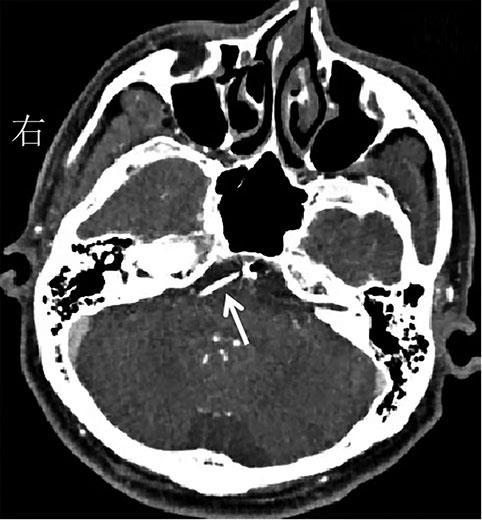

• 舞蹈症-棘红细胞增多症的早期识别和筛查

2022, 47(7):866-870. DOI: 10.13406/j.cnki.cyxb.003039

摘要 (583) HTML (43) PDF 2.07 M (376) 评论 (0) 收藏

摘要:目的 探讨舞蹈症-棘红细胞增多症(chorea-acanthocytosis,ChAc)临床特点,为该病早期诊断提供思路和方法。方法 通过回顾性研究,总结ChAc临床特点。结果 符合舞蹈样运动障碍的患者中,ChAc占29%,确诊时间中位值为5.5年。患者的发病年龄为(33.57±12.23)岁;7例(100%)均有口腔运动障碍,4例(57%)出现癫痫(全面强直阵挛发作),6例(86%)出现腱反射减弱或消失,5例(71%)肌酸激酶增高;头颅磁共振可见尾状核尤其尾状核头(57%)和豆状核(29%)萎缩,侧脑室前角扩大(57%);正电子发射断层显像(positron emission tomography,PET)-电子计算机断层扫描(computed tomography,CT)可见双侧基底节区低代谢表现(43%)。所有患者均可见棘红细胞比例大于3%,基因测序29%可发现责任基因VPS13A突变。结论 ChAc的确诊时间长,口腔运动障碍、肌酸激酶增高有助于尽早识别。建议舞蹈症患者常规进行2次以上的外周血涂片,进而再进行基因检测确立诊断。